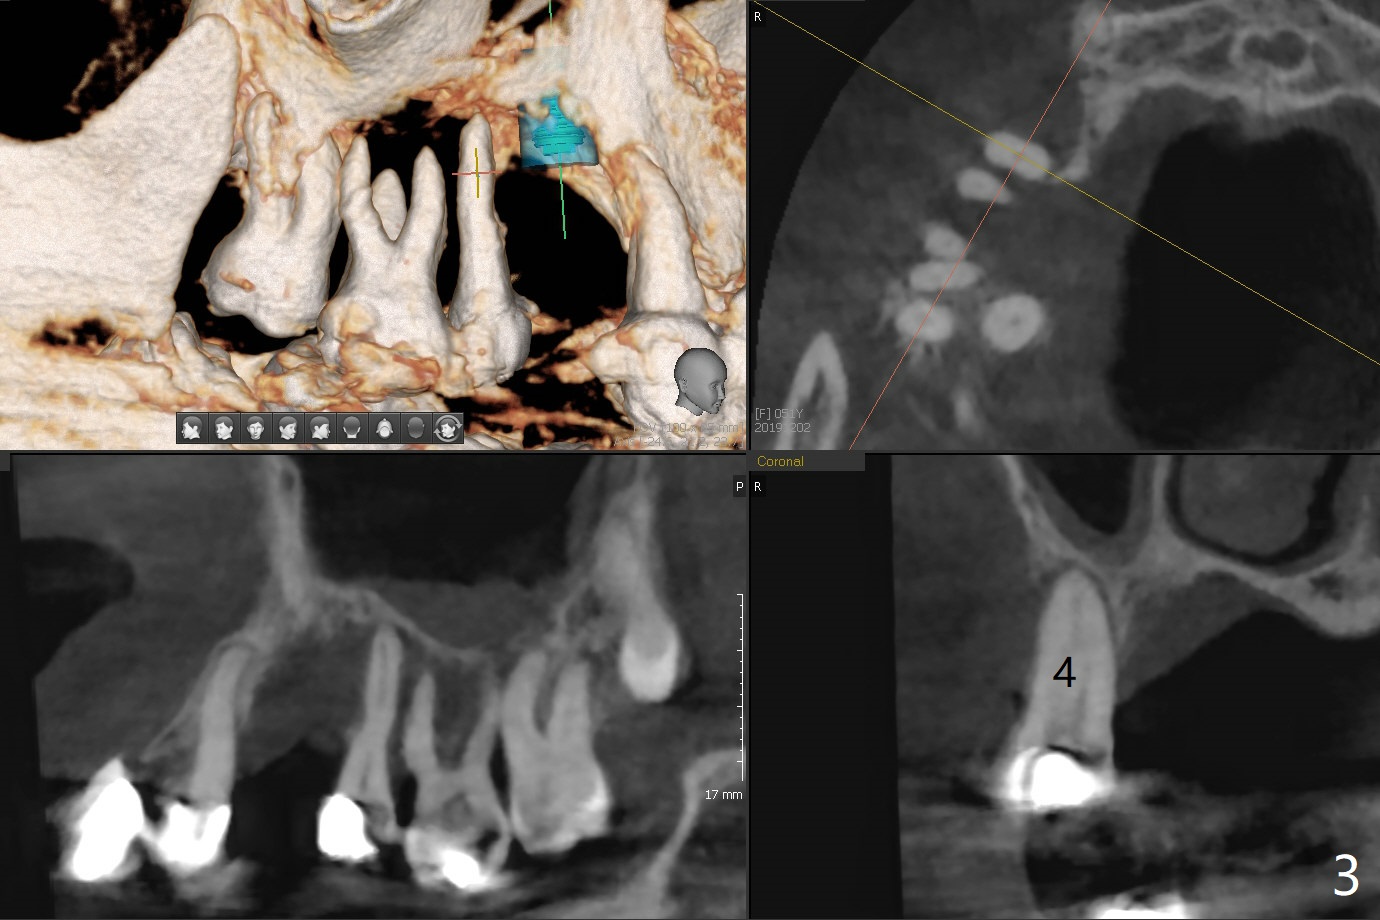

A 51-year-old woman has poor dentition with chronic periodontitis (Fig.1). She has financial constraint, but refuses RPD, insisting upon UR posterior implants first. After discussion of severe bone loss, she agrees with bone graft first (Fig.2-4). Since the bone atrophy is the most severe at #3 (Fig.5 coronal section; L: lingual), sinus lift (Fig.6 arrow) is conducted after extraction (black). Use sticky bone (Fig.7 red circles) and Titanium-reinforced Cytoplast (white) for socket preservation. Or if Magicore is able to achieve primary stability (Fig.8 green), an abutment (pink) will be placed for an immediate provisional (white). The latter are capable of holding bone graft in place. Since bone loss at #2 and 4 is less severe (Fig.9 sagittal section), their roots will act as walls to keep bone graft (Fig.11) in place after #3 extraction (Fig.10).